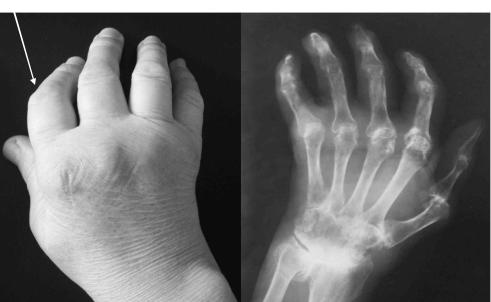

Процесс обычно симметричен и охватывает суставы обеих кистей (рис.1-2) и обеих стоп практически одновременно.

Рис.1-2. Ранний РА. Обращает на себя внимание симметричные артриты проксимальных межфаланговых (палец формы «веретена») и пястно-фаланговых суставов.

С течением времени у пациентов формируется ревматоидная кисть: ульнарная девиация пястно -фаланговых суставов, обычно развивающаяся через 1—5 лет от начала болезни (рис.1-3); поражение пальцев кистей по типу «бутоньерки» (сгибание в проксимальных межфаланговых суставах) или «шеи лебедя» (переразгибание в проксимальных межфаланговых суставах) (рис.1-4); деформация кисти по типу «пуговичная петля» (рис.1-4, 1-5).

Рис. 1-3. Ульнарная девиация («плавник моржа»)